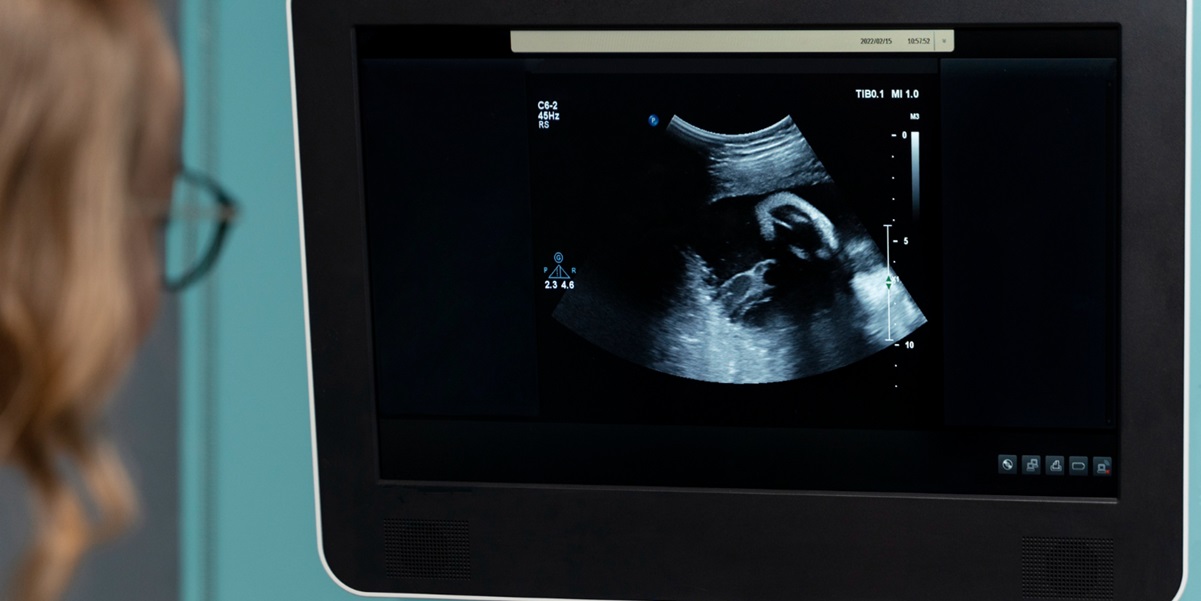

Cara deteksi fetus in fetu

Cara deteksi fetus in fetu satu-satunya yang efektif yaitu dengan melakukan prosedur CT scan dan pemeriksaan radiografi. Kedua jenis pemeriksaan tersebut dapat menunjukkan ada atau tidaknya keberadaan janin di dalam tubuh. Sebelum melakukan pemeriksaan ini, dokter biasanya akan meminta untuk konsultasi kesehatan terlebih dahulu untuk mengetahui lebih lanjut gejala yang dialami.